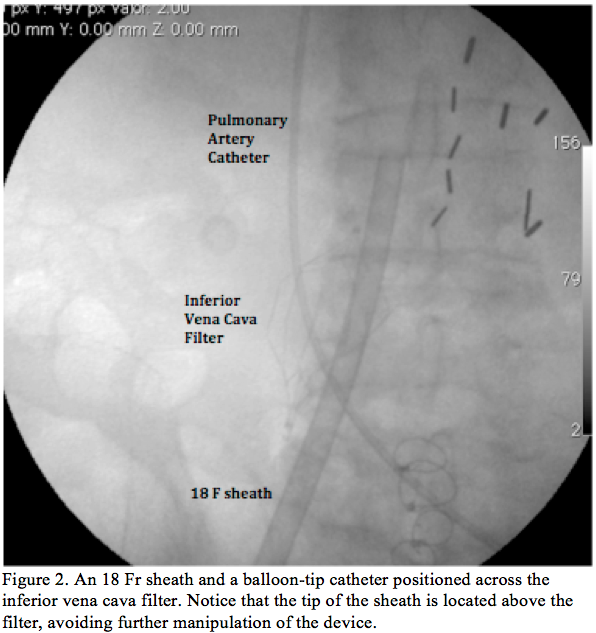

Procedure 1. After adequate skin preparation, access was gained from both femoral veins. Contrast media injection from the right femoral vein showed patency of the IVCF and no evidence of thrombus related to the device (Figure 1). After advancing a very soft 0.035˝ wire (Benson wire; Parkmore Business) through the IVCF, a 6 Fr balloon-tip catheter (Arrow International Inc) was placed across the filter and the wire was exchanged through this catheter for an extra-stiff wire. Over this wire, a 25 cm, 18 Fr sheath was introduced and positioned across the IVCF under strict fluoroscopic guidance, leaving the sheath

tip above the IVCF. Then, the Benson wire was introduced from the left femoral vein and crossed the IVCF and the 6 Fr balloon-tip catheter was placed through the IVCF into the left pulmonary artery (Figure 2). All manipulations for the valvuloplasty were done through the 25 cm, 18 Fr sheath, obviating the need for further crossing the filter. Standard PMV was performed with a 26 mm Inoue balloon, achieving a satisfactory result. Radioscopy-guided retrieval of the pulmonary artery catheter and the PMV catheter through the IVCF was carefully performed, showing no evidence of IVCF dislodgment (Figure 3). Final contrast